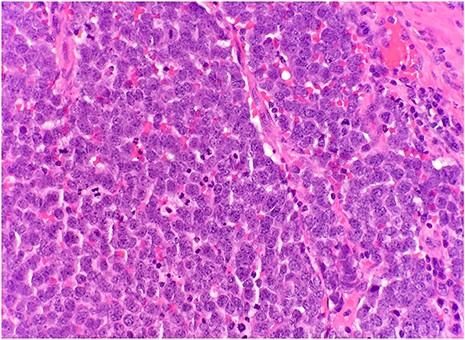

After surgical excision, specimen was received by pathology in formalin and consisted of a fragment of pink-tan dense tissue measuring 6.5 × 5.5 × 4 cm. The cut section revealed a fresh and necrotic surface. Microscopic examination revealed nests of monotonous round tumor cells with infiltration of the subcutis. Tumor cells had a scant eosinophilic cytoplasmic rim and round, vesicular nuclei with abundant mitotic figures (Fig. 1) and neuroendocrine features (CD56 and Synaptophysin positive) (Fig. 2). Immunohistochemical stain CK20 demonstrated paranuclear dot-like staining, consistent with MCC (Fig. 3). Negative staining for CD45 excluded lymphoma. The tumor demonstrated positive margins with vascular invasion.

Immunohistochemical stain CK20 demonstrated paranuclear dot-like staining (IHC × 20).

MCC originates in the dermis, but can expand into the epidermis [1]. The tumor is composed of strands or nests of monotonous small round blue cells with prominent nuclei and little cytoplasm. The cells have frequent mitoses with “salt and pepper” chromatin [4]. Immunohistochemistry (IHC) is used for the definitive diagnosis of MCC. CK20 stains in a paranuclear dot-like pattern in 80–90% of MCC cases due to clumping of intermediate filaments. MCCs frequently stain positive for neuroendocrine markers, such as chromogranin, synaptophysin and CD56. MCC stains negative for TTF-1 and CD45, which distinguishes it from small cell lung carcinoma and lymphoma, respectively [1, 4].